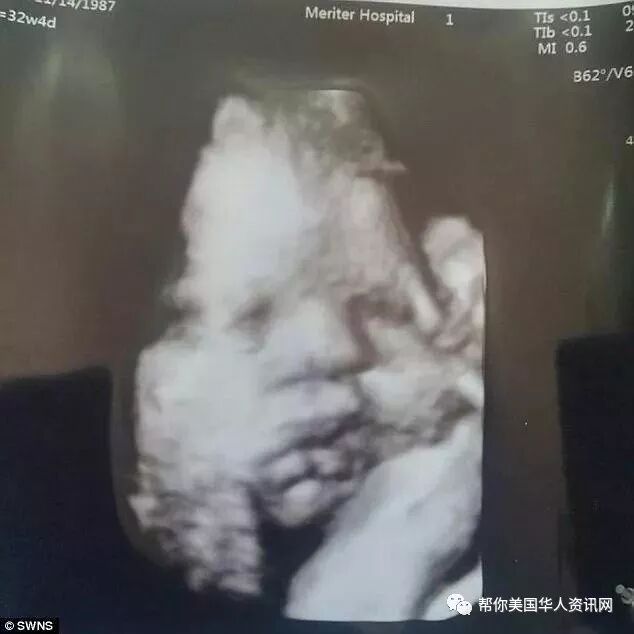

经过了长达七天的自然分娩失败之后,Kaci终于决定接受剖宫产,并于11月11日下午两点零五分产下了一个健康的孩子,他们给这个孩子起名为Phoenix。

Kaci说,当Phoenix被送到他怀里的那一刻,他觉得自己人生从来没有如此幸福过。